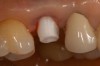

Figure 11 – Internal connection implant system – implant placed post-extraction

Figure 11

Figure 12 – Prefabricated zirconia abutment fitting the internal connection in Figure 11

Figure 12

Figure 13 – Zirconia abutment torque onto implant

Figure 13